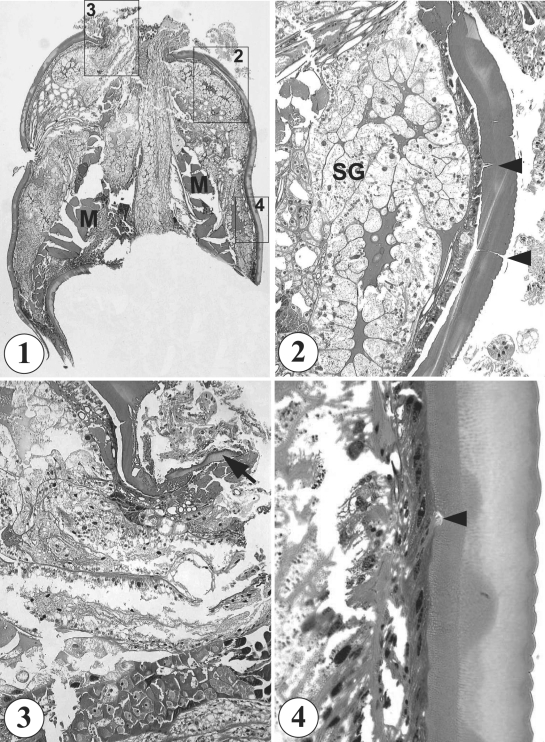

In light microscopic observations of the sections, the mass appeared to be a part of a round to elliptical-shaped organism (0.8 × 0.6 cm), and looked like a pentastomid, or an arthropod, without containing any structure of host origin (Fig. 1). It was finally identified as a species of hard tick, presumably belonging to family Ixodidae. It had a non-segmented body, well developed skeletal musculature of 160 µm in thickness in the middle part of the body (Fig. 1), well developed salivary glands in anterior half of the body (Fig. 2), and a capitulum (Fig. 3). Its external surface was covered with a thick cuticle of about 80 µm in thickness, which consisted of 5 layers, including an outermost thin layer with saw-like annulations, 3 inner layers of different thickness and structures, and the innermost layer with pore canals (Fig. 4). No legs were found sectioned.

Fig. 1-4

Histological sections of the tick extracted from the scalp of a Korean boy. 1. A whole section of the tick (up; capitulum side, down; tail side) showing its characteristic body contour, cuticle structures, and well developed musculature (M). H-E stain, × 40. 2. An enlarged view of box 2 in Fig. 1 showing well developed salivary glands (SG) and cuticle with pore canals (arrowheads). H-E stain, × 100. 3. An enlarged view of box 3 in Fig. 1, the capitulum side. A part of the capitulum (arrow) is seen sectioned. H-E stain, × 100. 4. An enlarged view of box 4 in Fig. 1 showing the characteristic saw-like cuticular surface and a pore canal. H-E stain, × 400.